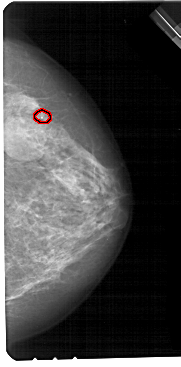

A_1705_1.RIGHT_MLO

RIGHT_CC LINES 5491 PIXELS_PER_LINE 2701 BITS_PER_PIXEL 12 RESOLUTION 43.5 OVERLAY

FILE: A_1705_1.RIGHT_CC.OVERLAY

TOTAL_ABNORMALITIES 1

ABNORMALITY 1

LESION_TYPE CALCIFICATION TYPE PLEOMORPHIC DISTRIBUTION CLUSTERED

ASSESSMENT 4

SUBTLETY 2

PATHOLOGY BENIGN

TOTAL_OUTLINES 1

BOUNDARY